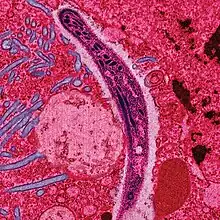

Le Plasmodium se présente sous la forme d'un protozoaire très petit (1 à 2 µm selon les formes). La coloration au May-Grünwald-Giemsa montre qu'il est constitué d'un cytoplasme bleu pâle entourant une vacuole nutritive claire et contenant un noyau rouge et du pigment brun-doré ou noir (hémozoïne).

Une première transformation arrondit cette forme « cryptozoïte » (du grec κρυπτός / kruptós, « caché ») en un élément uninucléé (avec un seul noyau) appelé trophozoïte qui est l'occasion pour le parasite de se multiplier directement (il en est toujours ainsi pour P. falciparum), par schizogonie, pendant une semaine à quinze jours aboutissant à un énorme schizonte (nom donné au protozoaire lorsqu'il devient actif après la phase d'incubation) de 40 à 80 μm. Ce corps bleu (parce que constitué d'un cytoplasme bleu pâle lorsqu'il est coloré au May-Grünwald-Giemsa) bourgeonne, tout en perdant de sa mobilité, de manière à émettre des vésicules, contenant les jeunes mérozoïtes qui seront transférés dans le sang, initiant ainsi le stade érythrocytaire, c'est-à-dire l'infection des globules rouges.

Au début de la longue phase sanguine[140] : les mérozoïtes s'accolent aux globules rouges, les envahissent, s'y développent en trophozoïtes puis s'y divisent (schizontes).

La lyse des hématies parasitées (éclatement des schizontes mûrs ou rosaces) libère de nouveaux parasites (mérozoïtes) qui contaminent à leur tour d'autres hématies. Cette destruction entraine aussi une libération des déchets du métabolisme plasmodial (pigments et débris cellulaires du globule rouge, ou hémozoïne), ces substances pyrogènes perturbent le fonctionnement de l'hypothalamus (production de cytokine comme le TNFα) et causent de fortes fièvres[143].